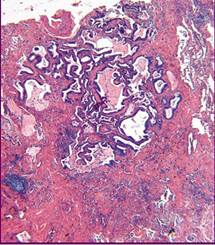

Комментарии: Эти патогистологические изменения обычно наиболее выражены в субплевральных и парасептальных зонах (Рис. 4). Интерстициальное воспаление обычно выражено умеренно, в виде очаговых инфильтратов, состоящих из лимфоцитов и плазматических клеток. В зонах фиброза могут встречаться так называемые фибробластические фокусы, состоящие из пролиферирующих фибробластов и миофибробластов (Рис. 5). «Сотовые» структуры представляют собой кистозные полости с фиброзной стенкой, обычно выстланные бронхиолярным эпителием, которые могут содержать слизь и клетки воспаления (Рис. 6).

Рис. 6. Обычная интерстициальная пневмония: "сотовые" структуры